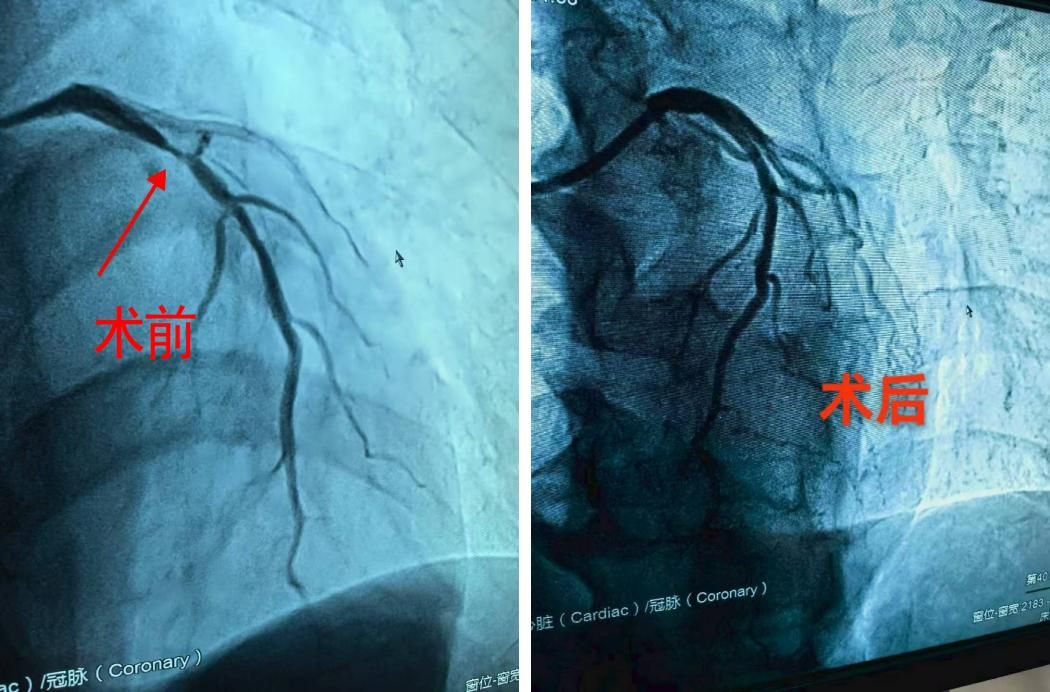

收到消息后,聂志敏通过微信交代好胸痛患者的注意事项,便立即赶回南昌市,为患者的转运和接收做好充分准备。下午5点患者到院,聂主任立刻为其安排了相关检查,经初步诊断,排除急性心梗,以“心绞痛”收治入院。在聂主任的建议下行经冠脉造影,造影结果明确显示:心脏冠状动脉前降支狭窄程度高达90%,这意味着供给心脏血液的主要通道已严重堵塞,生命随时可能受到威胁。

术前术后血流对比

基于准确的诊断和充分的术前准备,聂志敏当机立断,带领团队为患者实施了微创手术,送入药物球囊至病变处持续扩张,药物球囊成功打通了狭窄的血管,再次恢复血流,治疗成功!